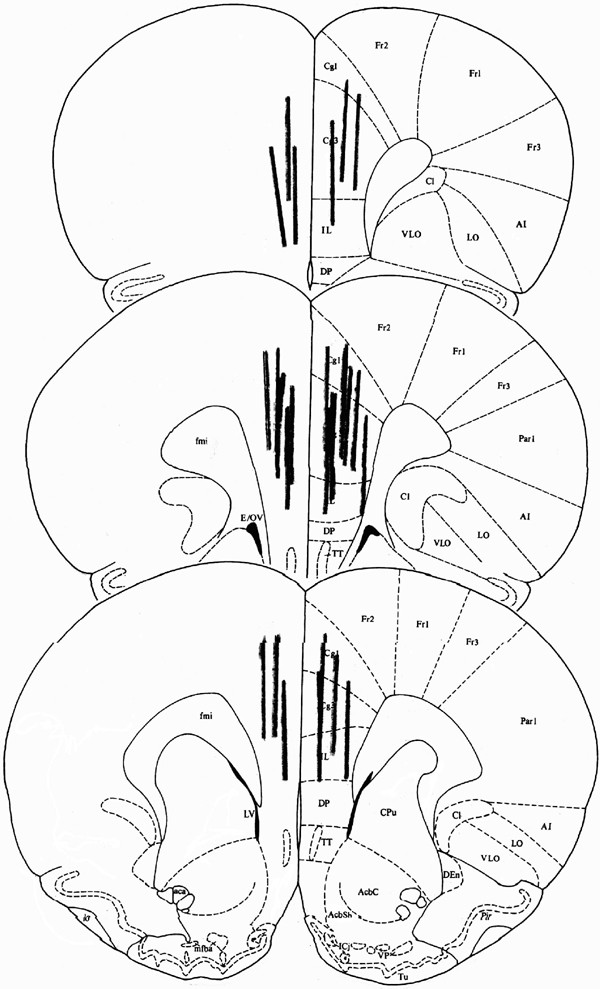

To verify probe placement, rats were anesthetized with 65 mg/kg sodium pentobarbital. The brains were removed, snap frozen in isopentane, and cryostat sectioned (40 μm) at −20°C. Sections were mounted on gelatin-treated slides, stained with cresyl violet, and coverslipped. Rats with probe placements outside of the mPFC were excluded from the analysis. Figure 1 shows probe placements of rats included in the analysis.

Figure 1

Placement of microdialysis probes in the mPFC.